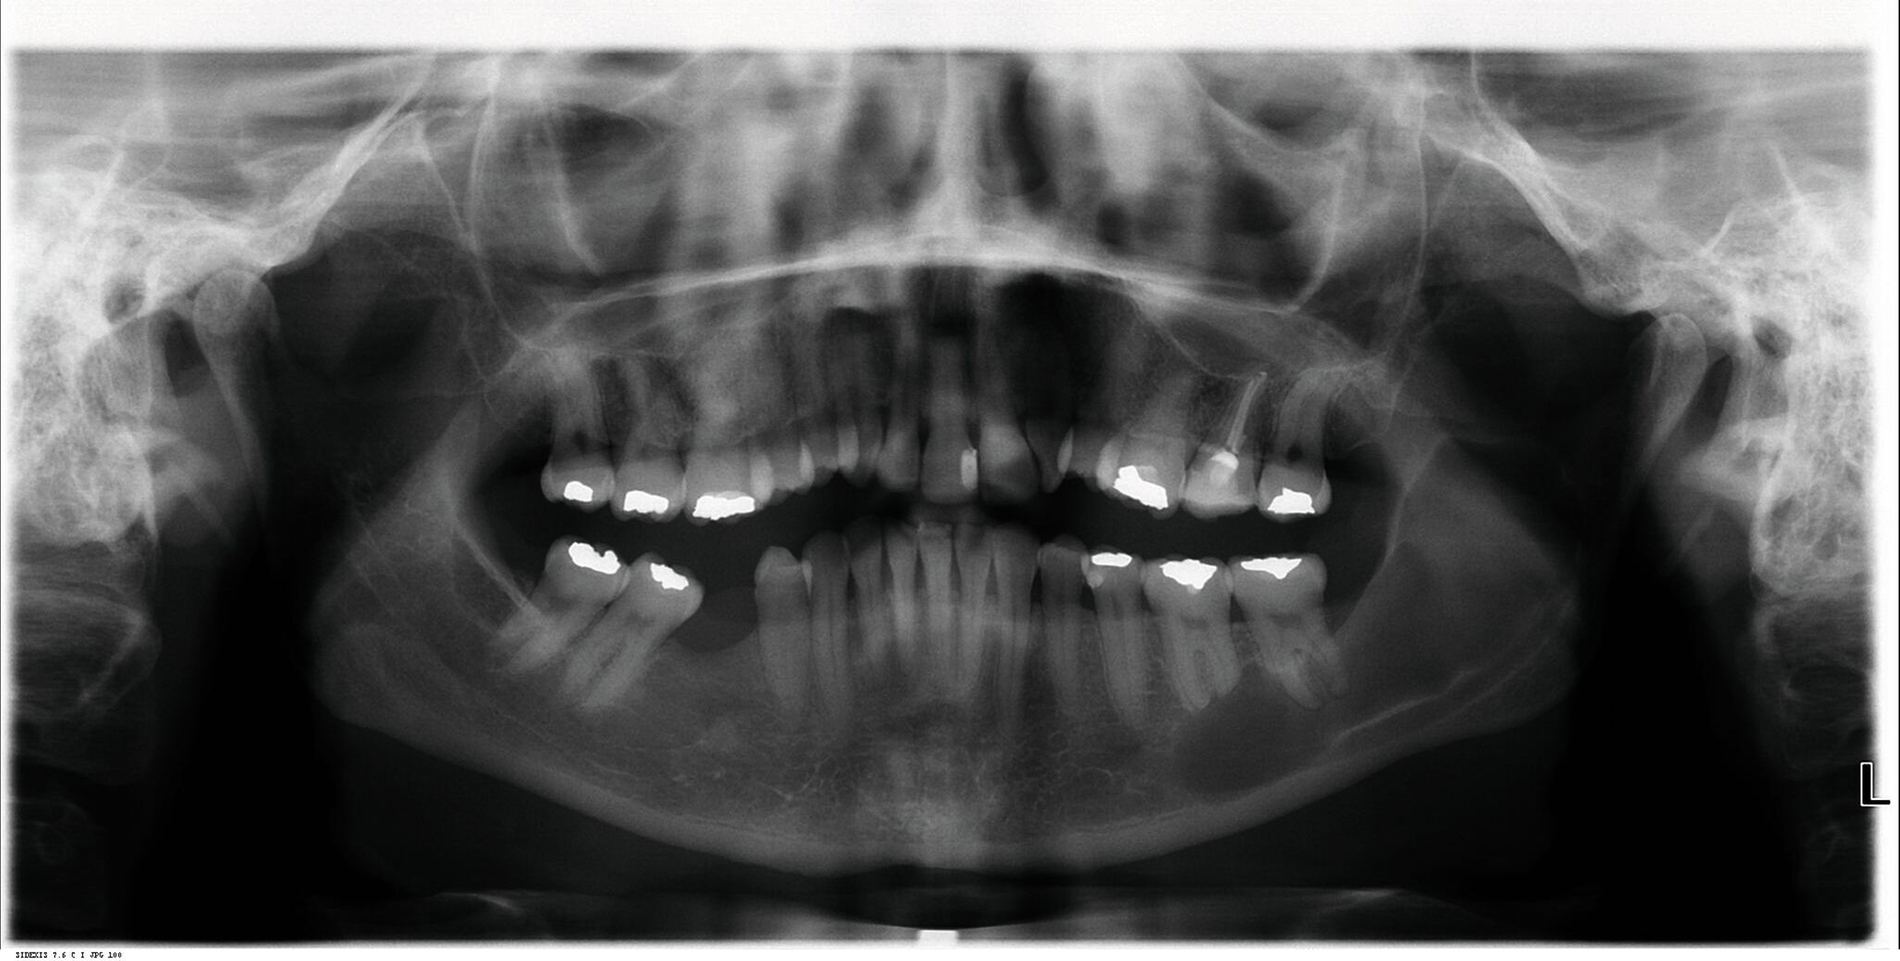

Im Rahmen der zahnärztlichen Routineuntersuchung fiel bei der seinerzeit 44-jährigen Frau eine zystische Läsion des linken aufsteigenden Unterkieferastes mit Ausdehnung nach mesial unter apikaler Beteiligung der Zähne 36 und 37 auf (Abbildung 1), woraufhin alio loco eine Zystektomie mit Wurzelspitzenresektion an den Zähnen 36 und 37 durchgeführt wurde.

Die histopathologische Beurteilung des enukleierten Zystenmaterials bestätigte die Verdachtsdiagnose einer Keratozyste. Als sich zwei Jahre später im Rahmen der regelmäßigen radiologischen Nachkontrollen erneut eine zystenähnliche Struktur im Bereich des linken aufsteigenden Unterkieferastes demarkierte, wurde die Patientin zur weiteren Diagnostik und Therapie an unsere Klinik überwiesen. Eine zusätzlich angefertigte digitale Volumentomografie (DVT) der betreffenden Region (Abbildung 2) erhärtete den klinischen Verdacht eines Keratozystenrezidivs, so dass zunächst eine erneute Zystektomie in Intubationsnarkose durchgeführt wurde.